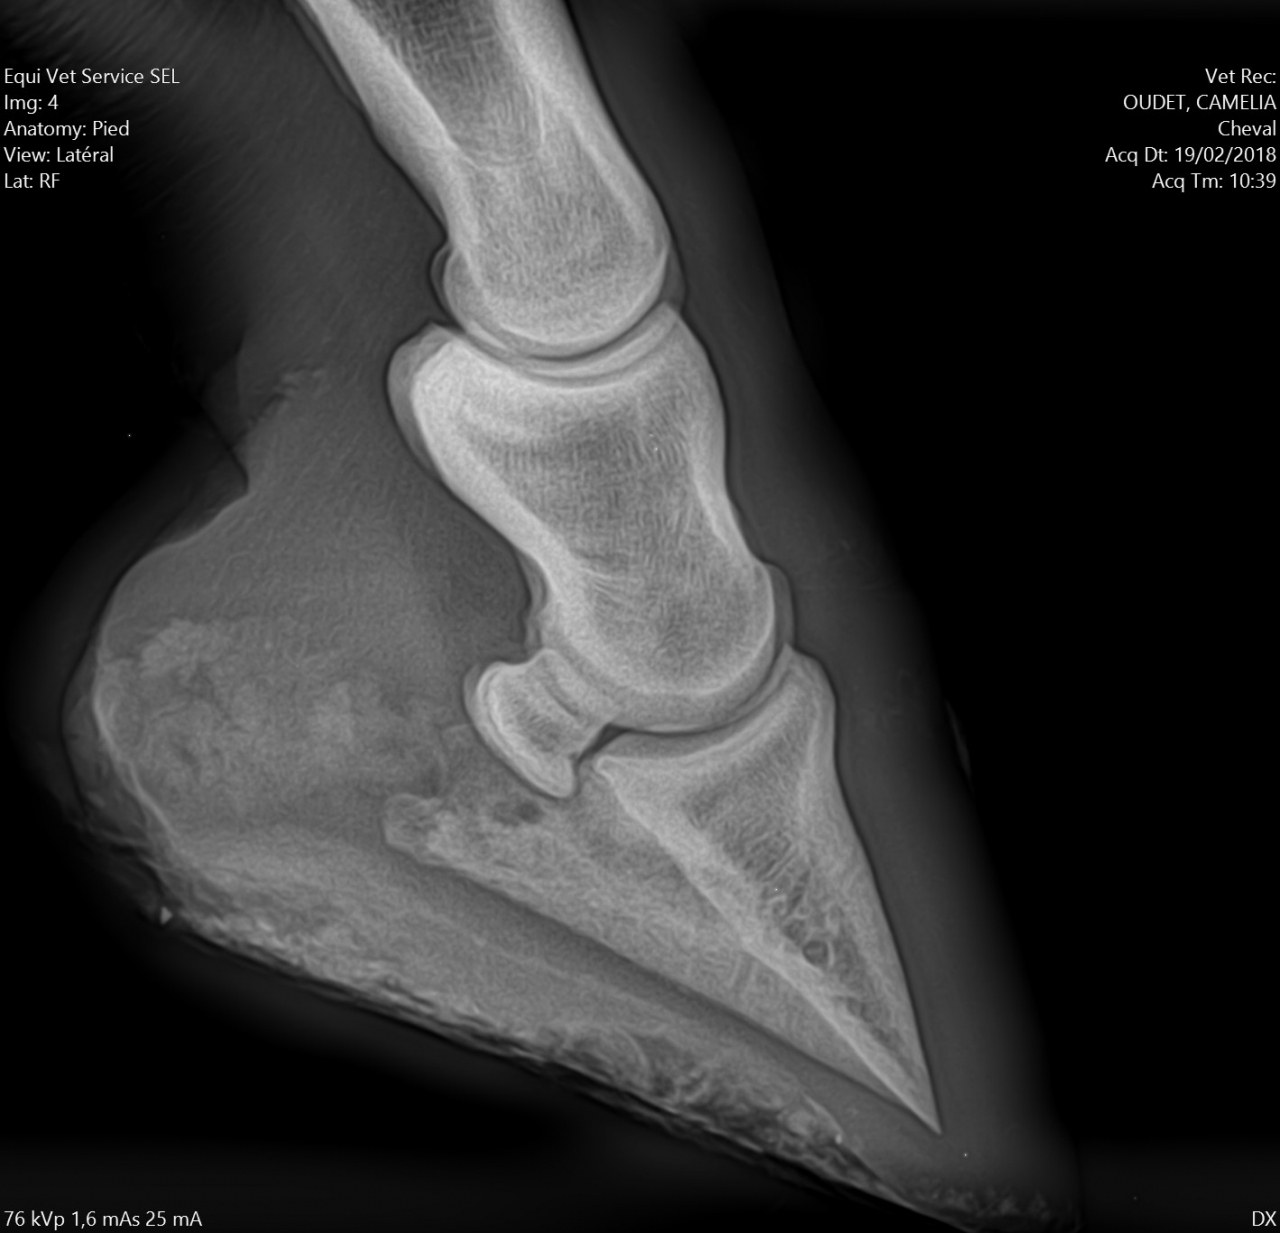

| Dire merci | Alors pour les fers, je ne suis pas une ayatollah du pieds nus, donc je l'ai évoqué avec la véto. Selon elle à ce stade, ça ferait plus de mal que de bien, pour les raisons suivantes : - jument confortable au pré, puisque terrains bien mous en ce moment - difficulté à ferrer vu ce qu'il "reste de pied", elle pense que ça va être un calvaire pour la jument de clouer - si jamais c'est un soucis de vascularisation, ça va plutôt amplifer le soucis Concernant les PHW, justement avec Kaline on était passé à une orthopédie à base de PHW, parce que pas moyen de faire tenir des fers compensés en talon dans la boue. Après ça dépend beaucoup de la locomotion du cheval, mais vu que Cam' n'est pas une foudre de guerre et que même si le pré est boueux on ne s'enfonce pas tant que ça, je suis plutôt confiante. Pour la biotine je veux bien des infos. Moi on m'a souvent dit que ça rendait l'organisme "paresseux" pour en produire lui même, et que si la flore digestive et les apports nutritionnels sont ok y a pas de raison d'avoir de carence ? J'aurais donc plutôt tendance à agir là dessus ? Les radios en spoilers pour celles et ceux que ça intéresse. Message édité le 19/02/18 à 17:18 |